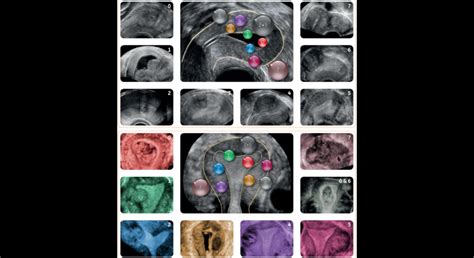

Ultrazvuk zameraný na diagnostiku neplodnosti sa vykonáva pomocou ultrazvukového vyšetrenia dutiny maternice s použitím kontrastného média (s pozitívnym alebo negatívnym kontrastom, čiže bielou alebo čiernou farbou na monitore). Cieľom je vylúčiť patologické štruktúry ako sú polypy, septá (prehrážky), zrasty alebo posúdiť stav jazvy po cisárskom reze.

Podmienkou úspešného vyšetrenia je načasovanie výkonu na prvé dni po skončení menštruácie, najneskôr do 10. dňa od začiatku menštruácie. Na začiatku výkonu sa vykonáva podrobné vyšetrenie maternice a vajíčkovodov pomocou klasického a 3D ultrazvuku. Následne sa aplikuje kontrastná pena, pri ktorej modrá šípka ukazuje na koniec vajíčkovodu, kde kontrastná pena vyteká do dutiny brušnej (červené šípky), čo je dôkaz priechodnosti vajíčkovodu.